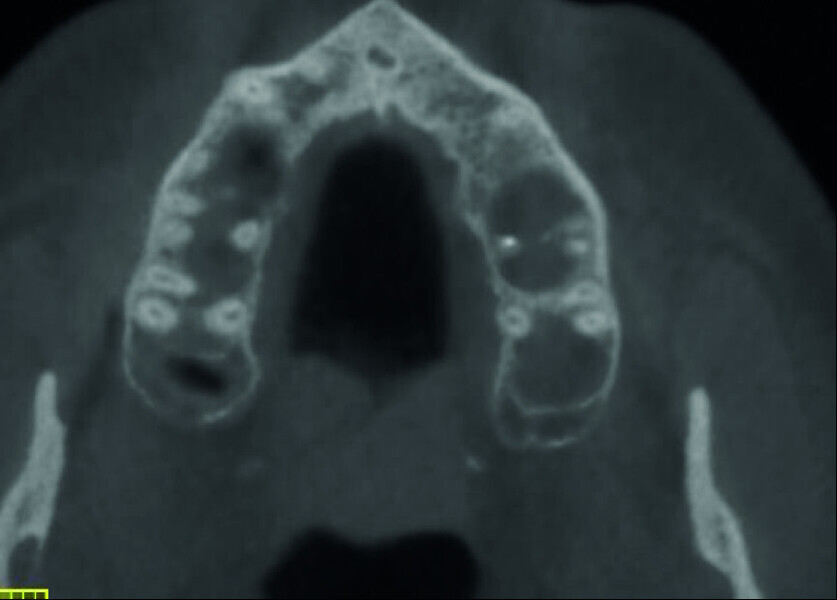

Maxillary sinus and root canal therapy complications